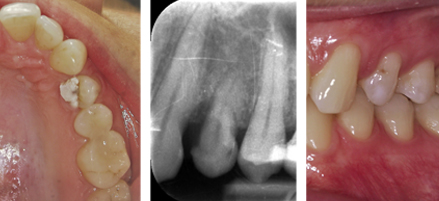

FAILING TOOTH

Card image Actual Practice Photographs ©Dr.Pavan Bopanna